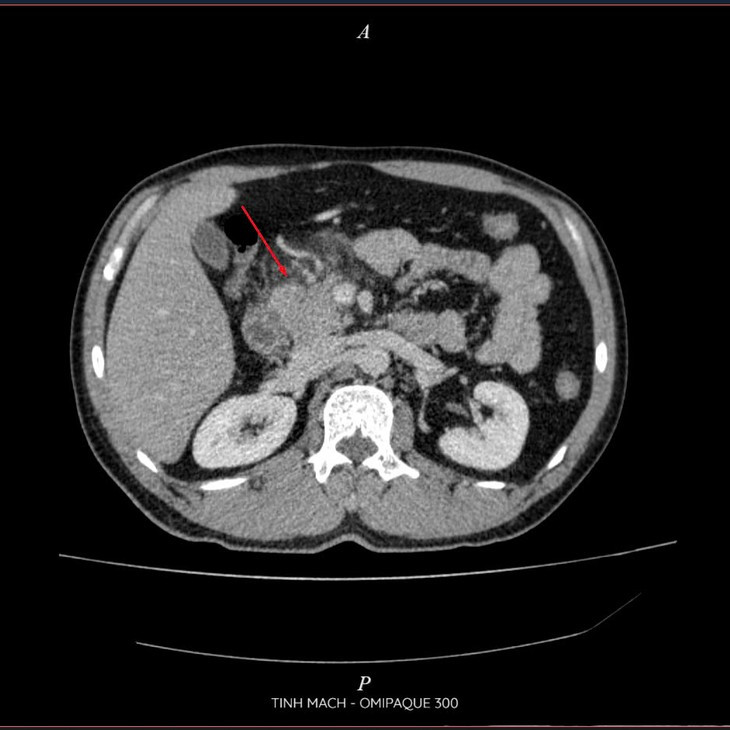

Viêm tụy cấp trên phim chụp - Ảnh BVCC

Kết quả chụp CT Scanner đa dãy ổ bụng có thuốc cho thấy: Hình ảnh viêm tụy cấp Balthazar D, mCTSI 4 điểm, xét nghiệm máu triglycerid >73 mmol/ l, khí máu có tình trạng toan Lactat>2. Nhận thấy đây là tình trạng viêm tụy cấp nặng do tăng triglyceride, các bác sĩ khoa Hồi sức cấp cứu Bệnh viện Đa khoa Hùng Vương đã tiến hành lọc máu hấp phụ cho bệnh nhân với mục tiêu là giảm triglycerid, và giảm phản ứng viêm.